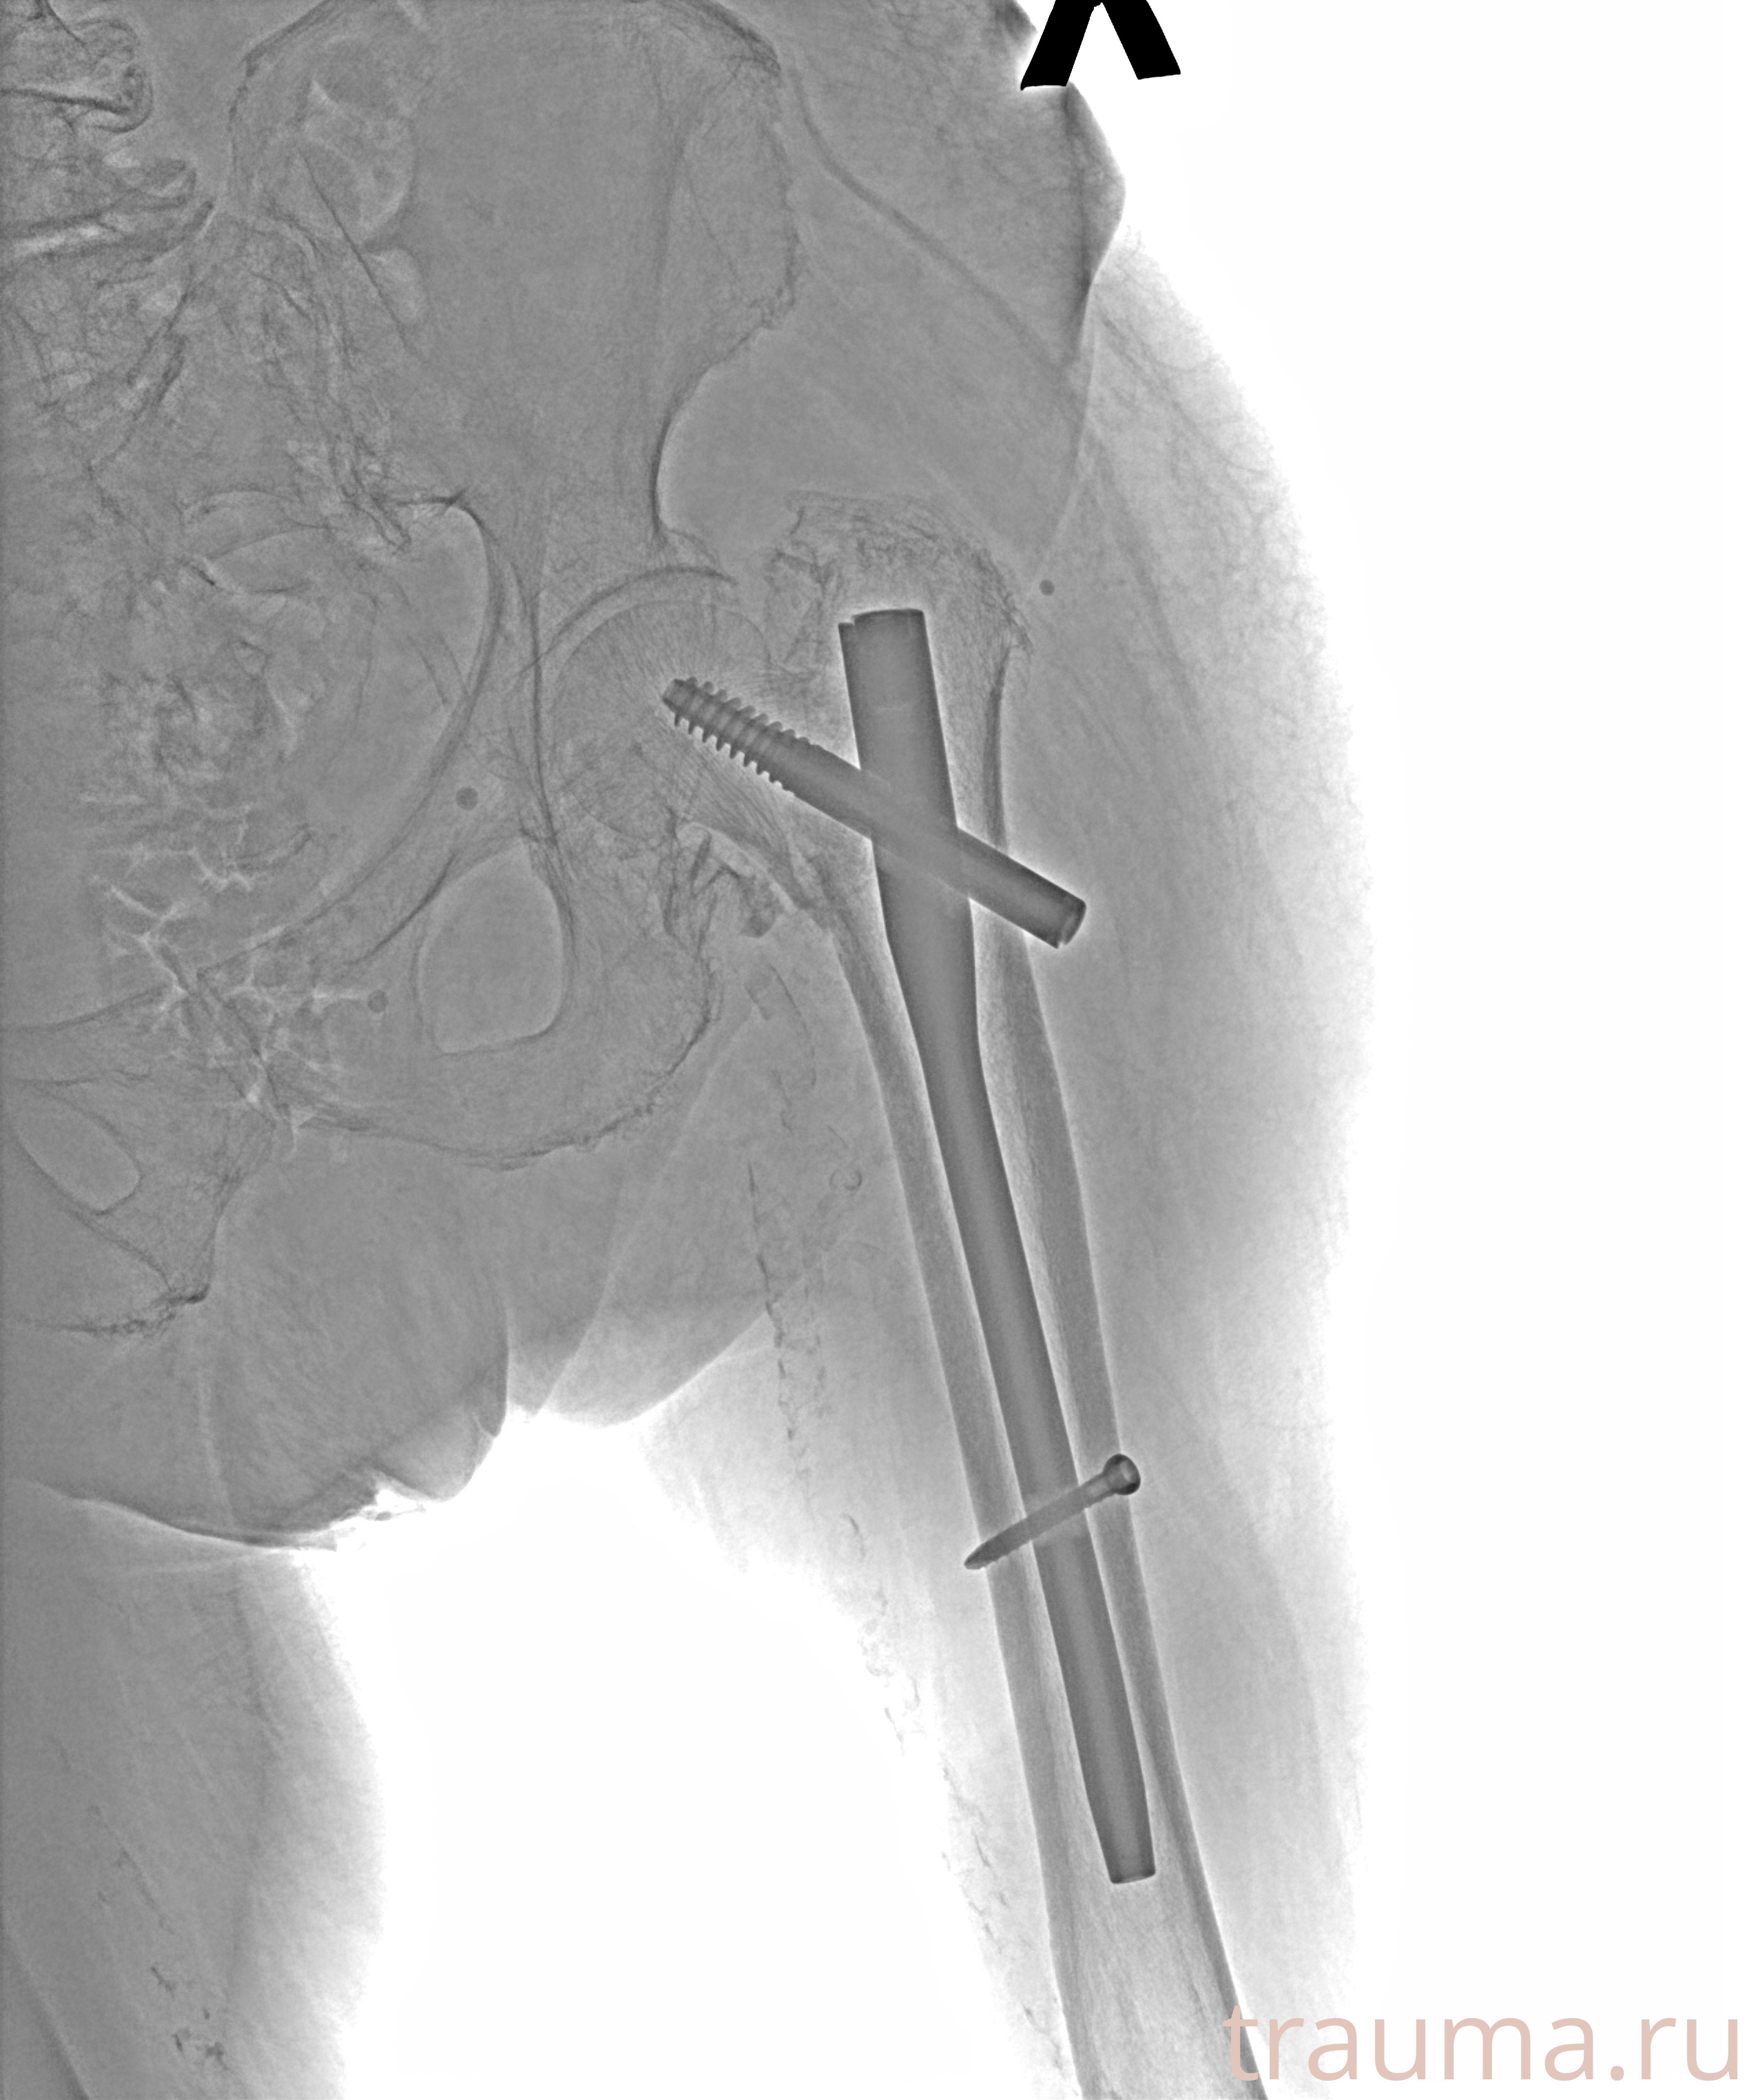

Рентгенограммы